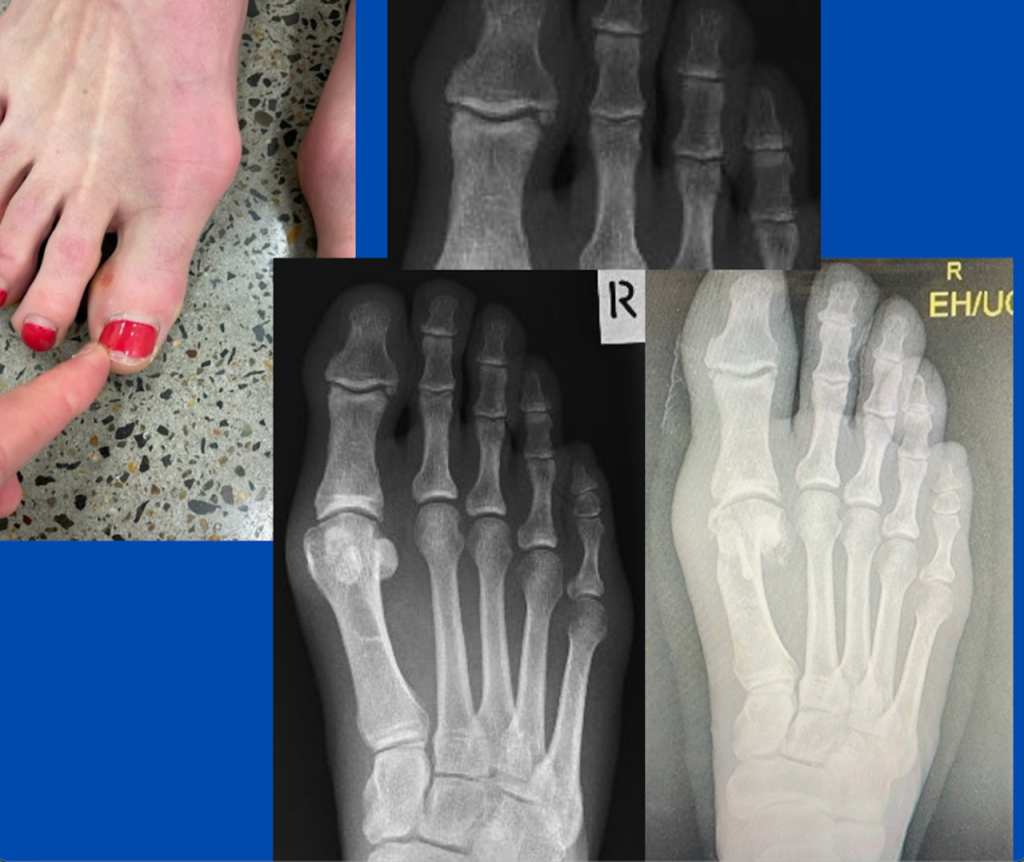

Minimally-invasive surgery (bunion and lateral hallux IPJ)

Blog's main page The images are from a case that underwent surgery a few weeks ago. The patient had a painful 1st MTPJ, but the main symptoms were felt on the lateral hallux and medial 2nd toe, involving pain and a corn formation. The conservative care had failed to provide enough relief. Note the signs of [...]

Interdigital corn

Blog's main page This would present at a podiatry practice on a regular occurrence. This case was in a 27-year-old, who had been suffering from a lateral 5th toe corn (heloma durum), however, an interdigital corn (heloma molle) on the medial 5th toe was most symptomatic. Symptoms were marked and hard to control, and the patient, [...]